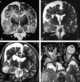

Hemiatrophy

Parry–Romberg syndrome (PRS) is a rare disease characterized by progressive shrinkage and degeneration of the tissues beneath the skin, usually on only one side of the face (hemifacial atrophy) but occasionally extending to other parts of the body. An autoimmune mechanism is suspected, and the syndrome may be a variant of localized scleroderma, but the precise cause and pathogenesis of this acquired disorder remains unknown. [Source: Wikipedia ]